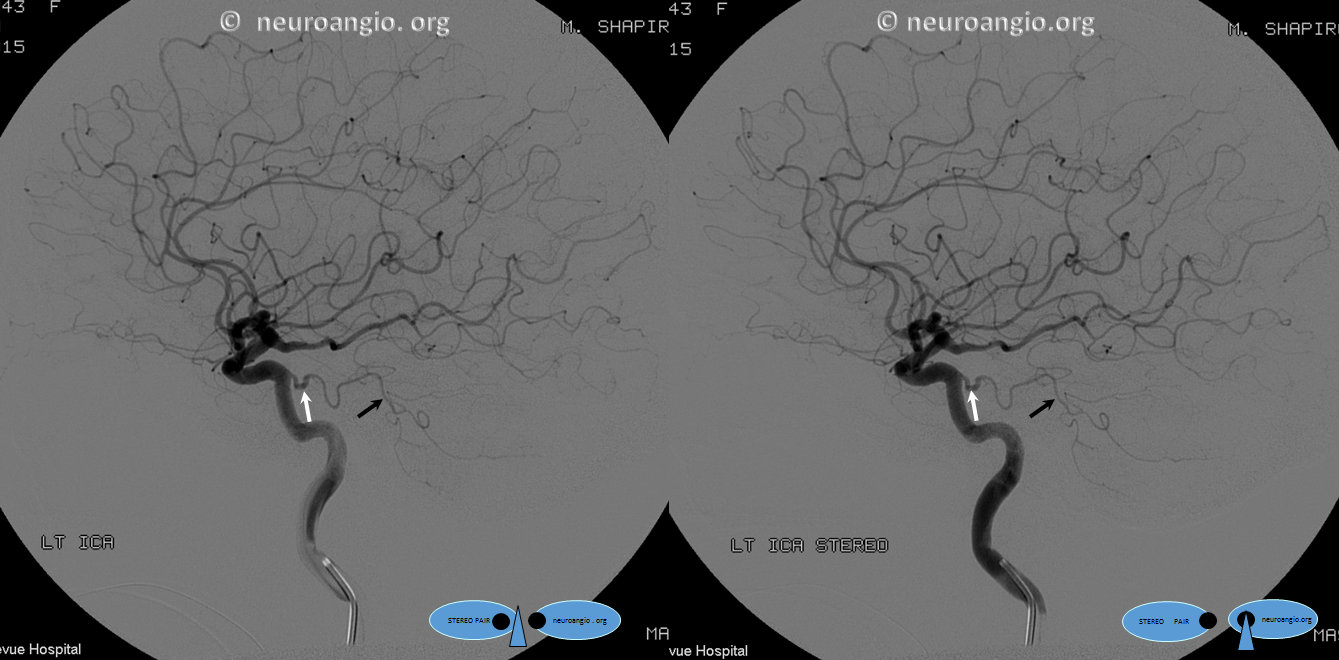

In this variant, the trigeminal artery (white arrow), supplies the lateral cerebellar territory classically belonging to the AICA In the Saltzman classification, this corresponds to Type IIIB

Anaglyph

AP view of carotid injections showing the AICA (black arrow), with corresponding wedge-shaped void of its territory seen on the right vert injection. Notice fetal disposition of both PCOMs.